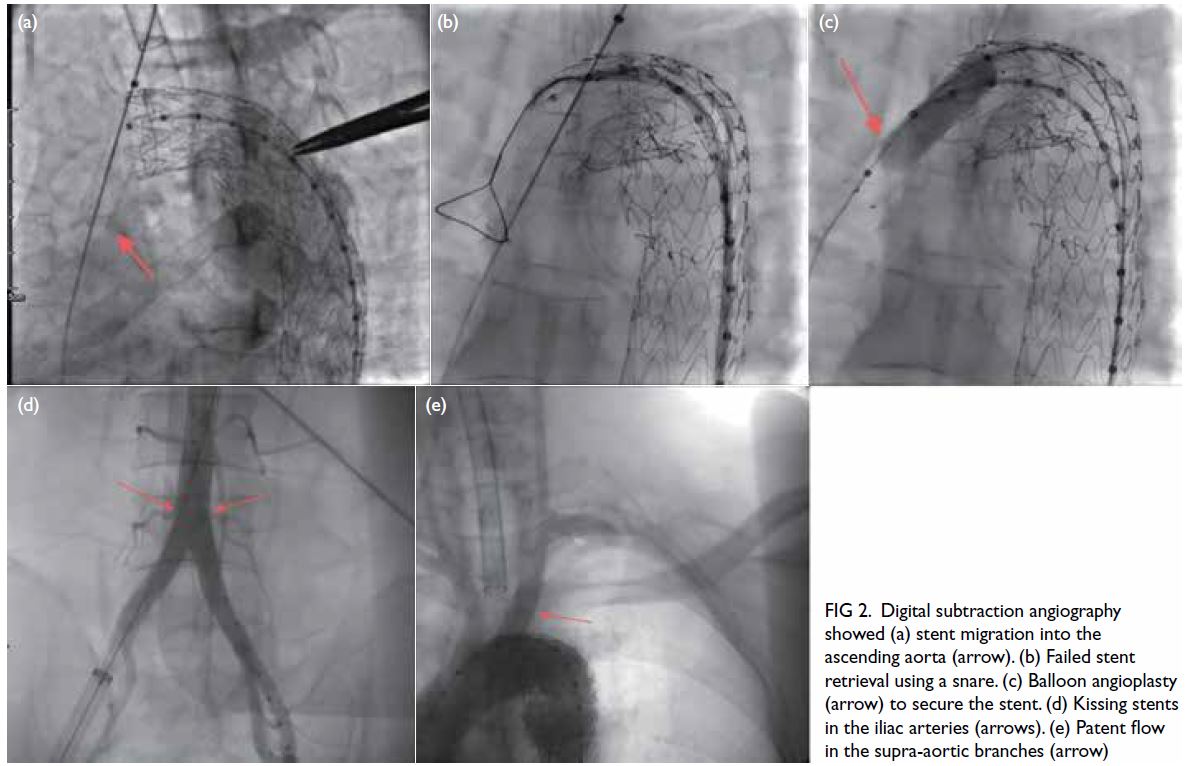

Figure 2. Digital subtraction angiography showed (a) stent migration into the ascending aorta (arrow). (b) Failed stent retrieval using a snare. (c) Balloon angioplasty (arrow) to secure the stent. (d) Kissing stents in the iliac arteries (arrows). (e) Patent flow in the supra-aortic branches (arrow)

Initial attempts to retrieve the stent with a

snare catheter and drag it to the femoral artery

were unsuccessful (Fig 2b). Subsequently, a single-curved

catheter and hydrophilic guidewire were

used to selectively cannulate the migrated stent. A

balloon catheter was then advanced into the stent

and inflated to secure firm attachment, allowing

successful traction of the stent into the right iliac

artery (Fig 2c).

To restore cerebral perfusion, a second balloon-expandable

stent (10 mm × 40 mm) [Express; Boston

Scientific, Marlborough [MA], US] was deployed

in the left common carotid artery to complete the

chimney stent placement. To prevent contralateral

flow obstruction and acute ischaemia in the left

lower limb due to the right iliac stent, an identical

stent was placed via the left femoral artery, creating

a kissing stent configuration in the iliac arteries (Fig 2d). Final angiography confirmed the absence of any

endoleak and demonstrated patent blood flow in the

aortic arch branch vessels and both iliac arteries (Fig 2e).